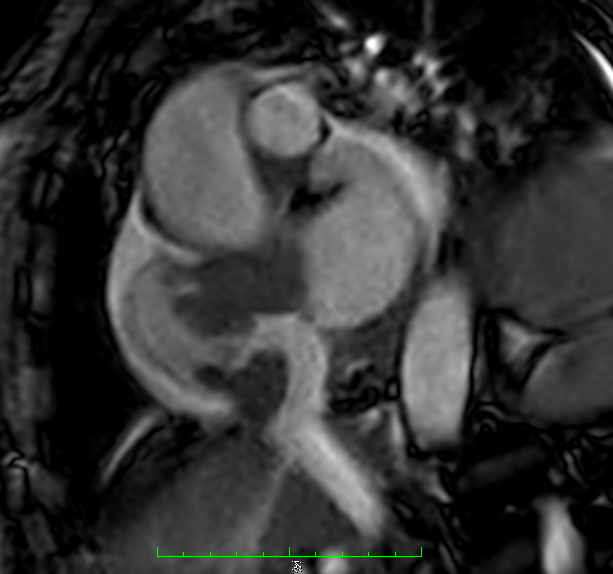

Four Chamber showing the mass projection to vital structures